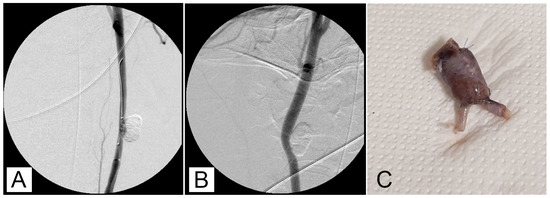

One possible method of cleaning a microcatheter lumen is to flush it with Lipiodol®. Nevertheless, it was occasionally discovered that GEL remained in the hub section of a microcatheter, making guidewire insertion challenging when the microcatheter was reinserted using a guidewire. Another microcatheter was needed in this case. In 15 of the 18 aneurysms, post-packing angiography showed nearly full aneurysm packing (Figure 1).

Figure 1. (A) Carotid angiography shows the aneurysm before embolization. (B) Attempted embolization using GEL 2:0, 5:1, via a microcatheter inserted into the microaneurysm, with balloon protection (C).